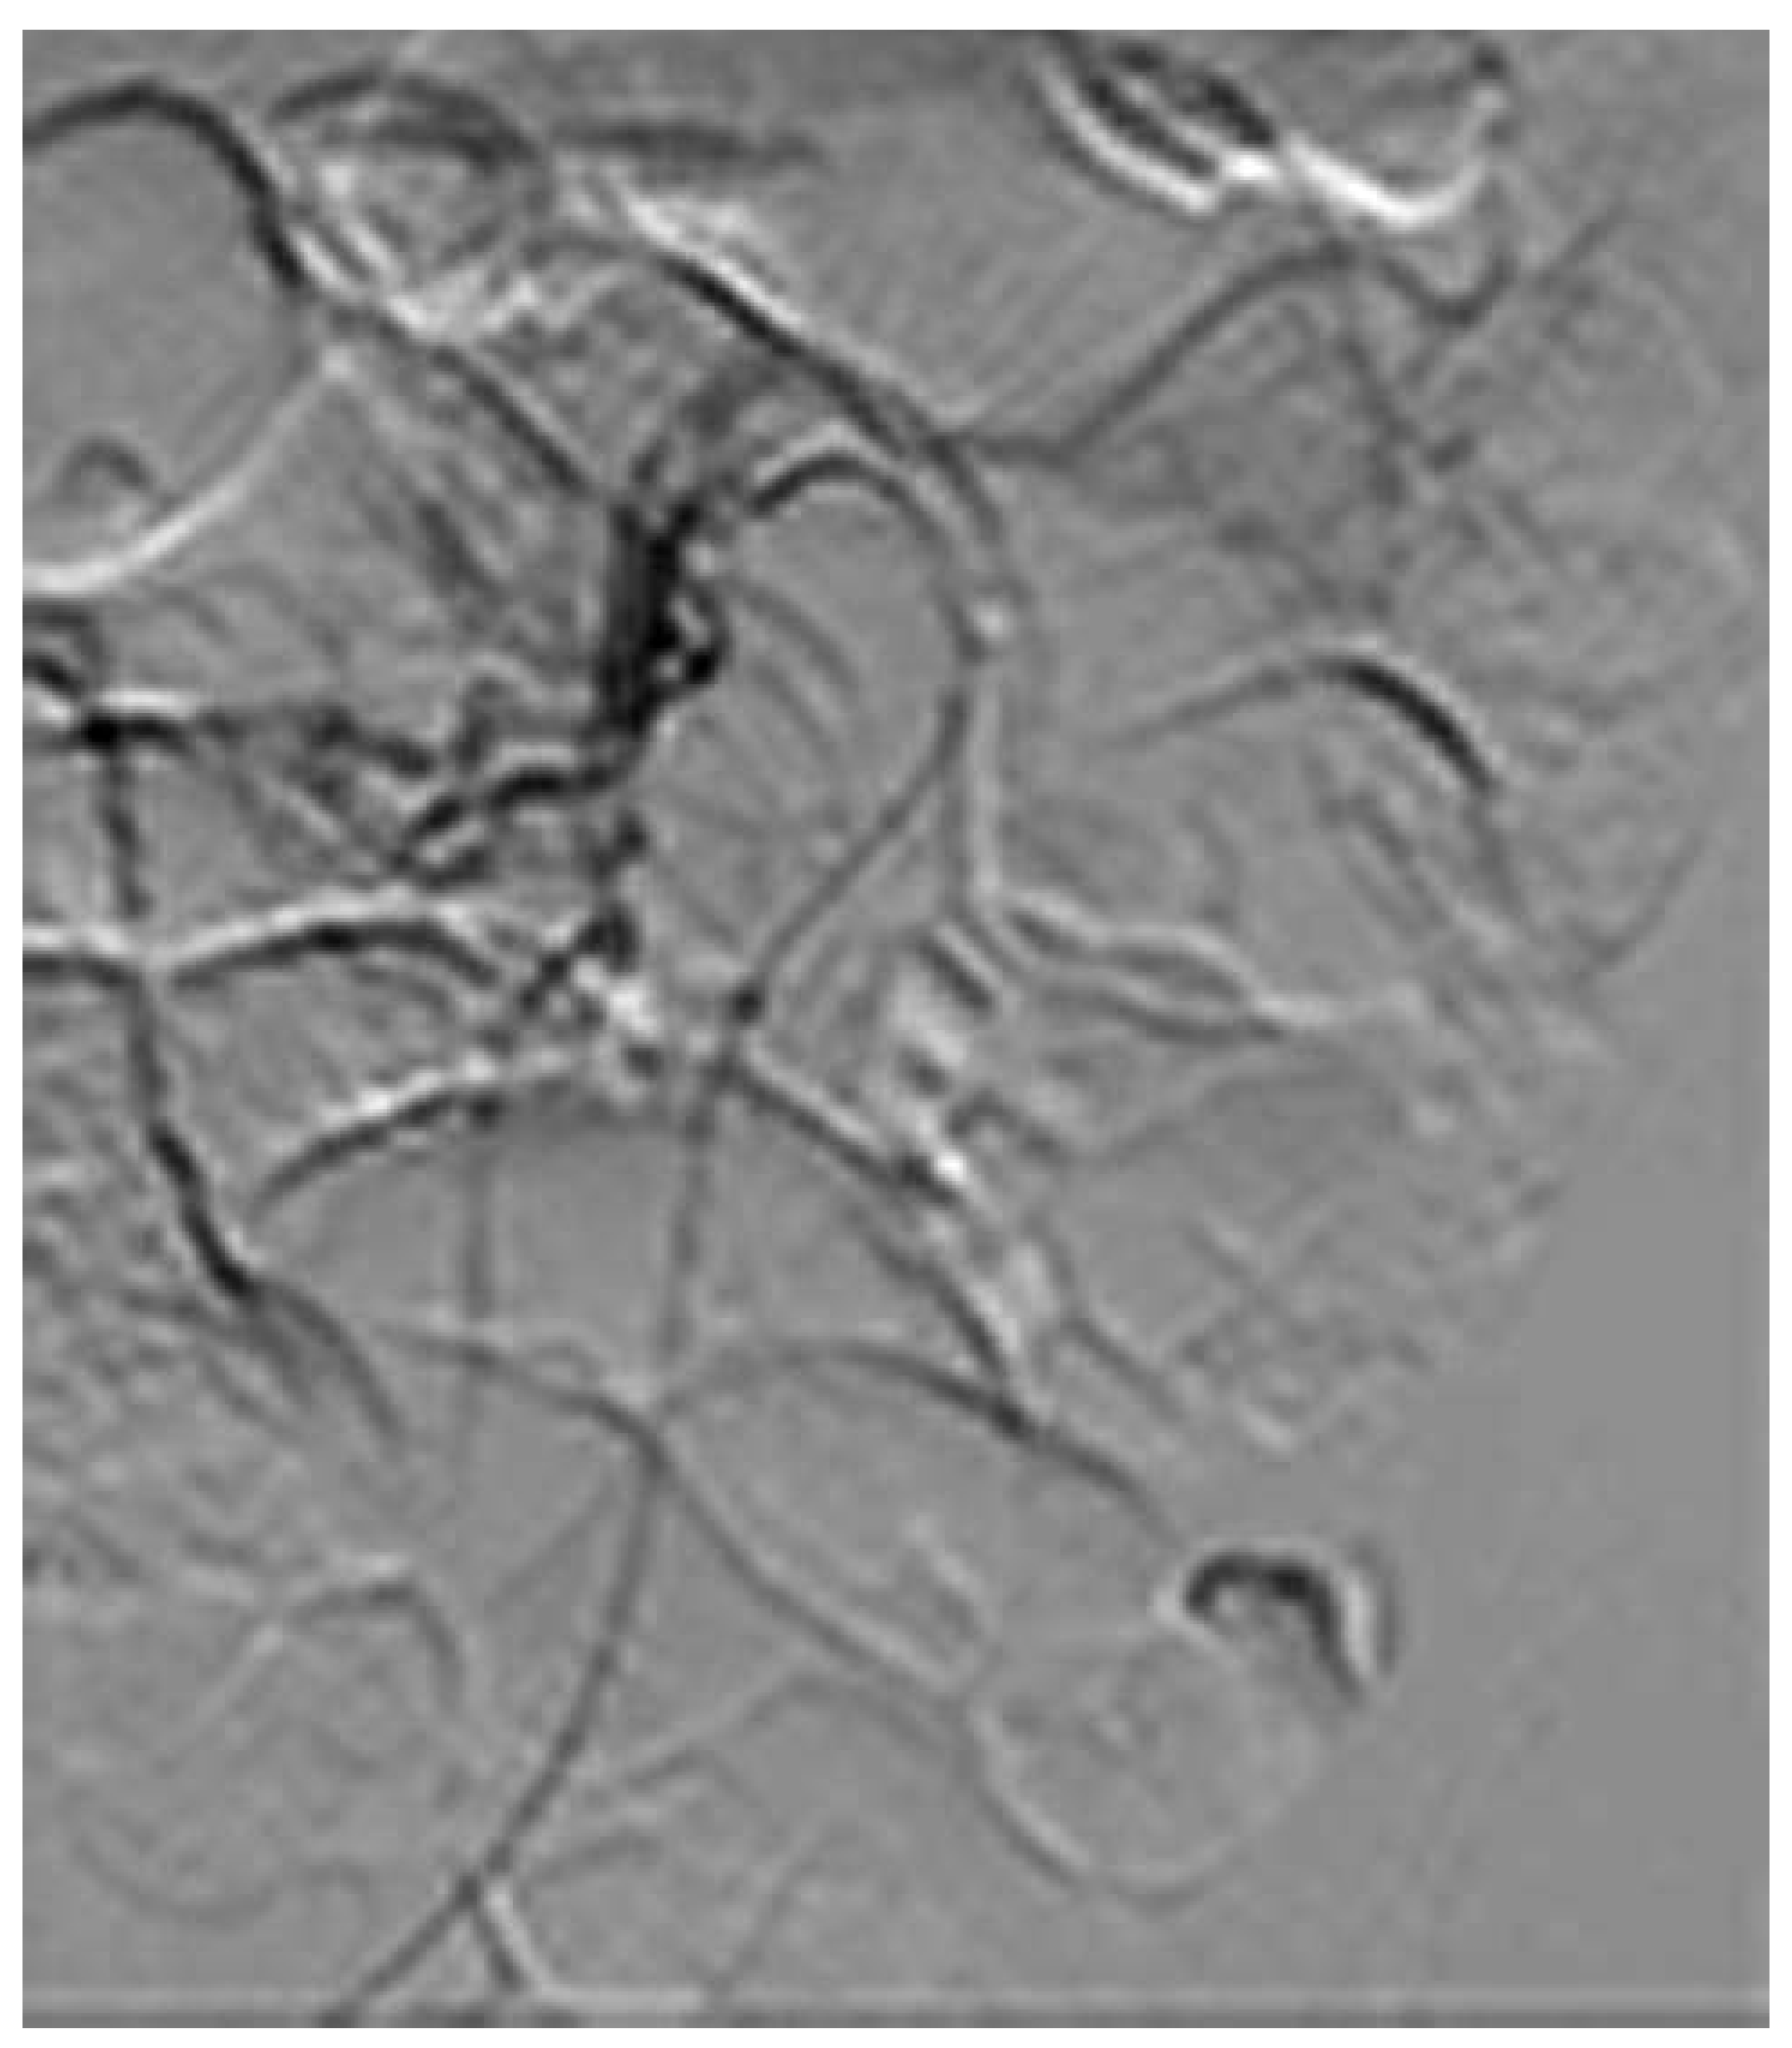

Endovascular Treatment of a Complex Type B Aortic Dissection

Case report